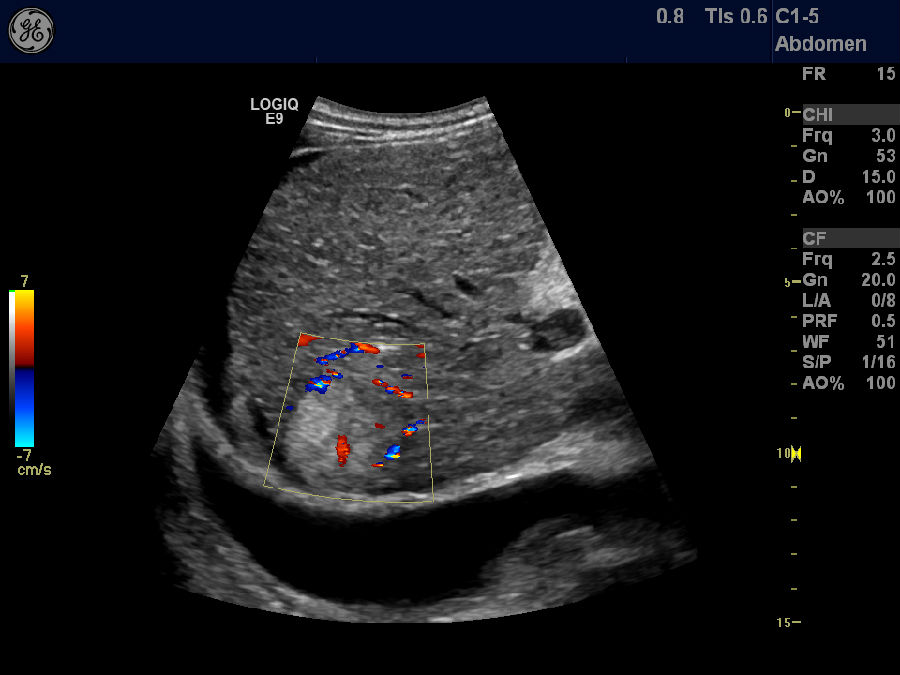

肝硬化、腹水

肋间斜切,彩色多普勒显示门静脉血栓,肝硬化,腹水